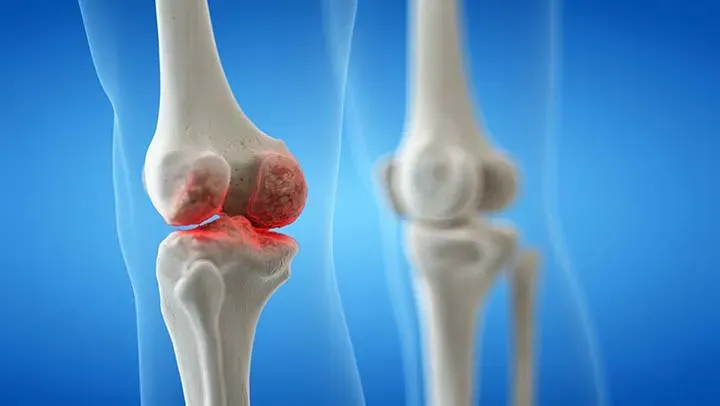

Knee Replacement

Knee replacement, also known as knee arthroplasty, is a surgical procedure performed to relieve pain and restore function in severely diseased knee joints. It involves removing damaged cartilage and bone...